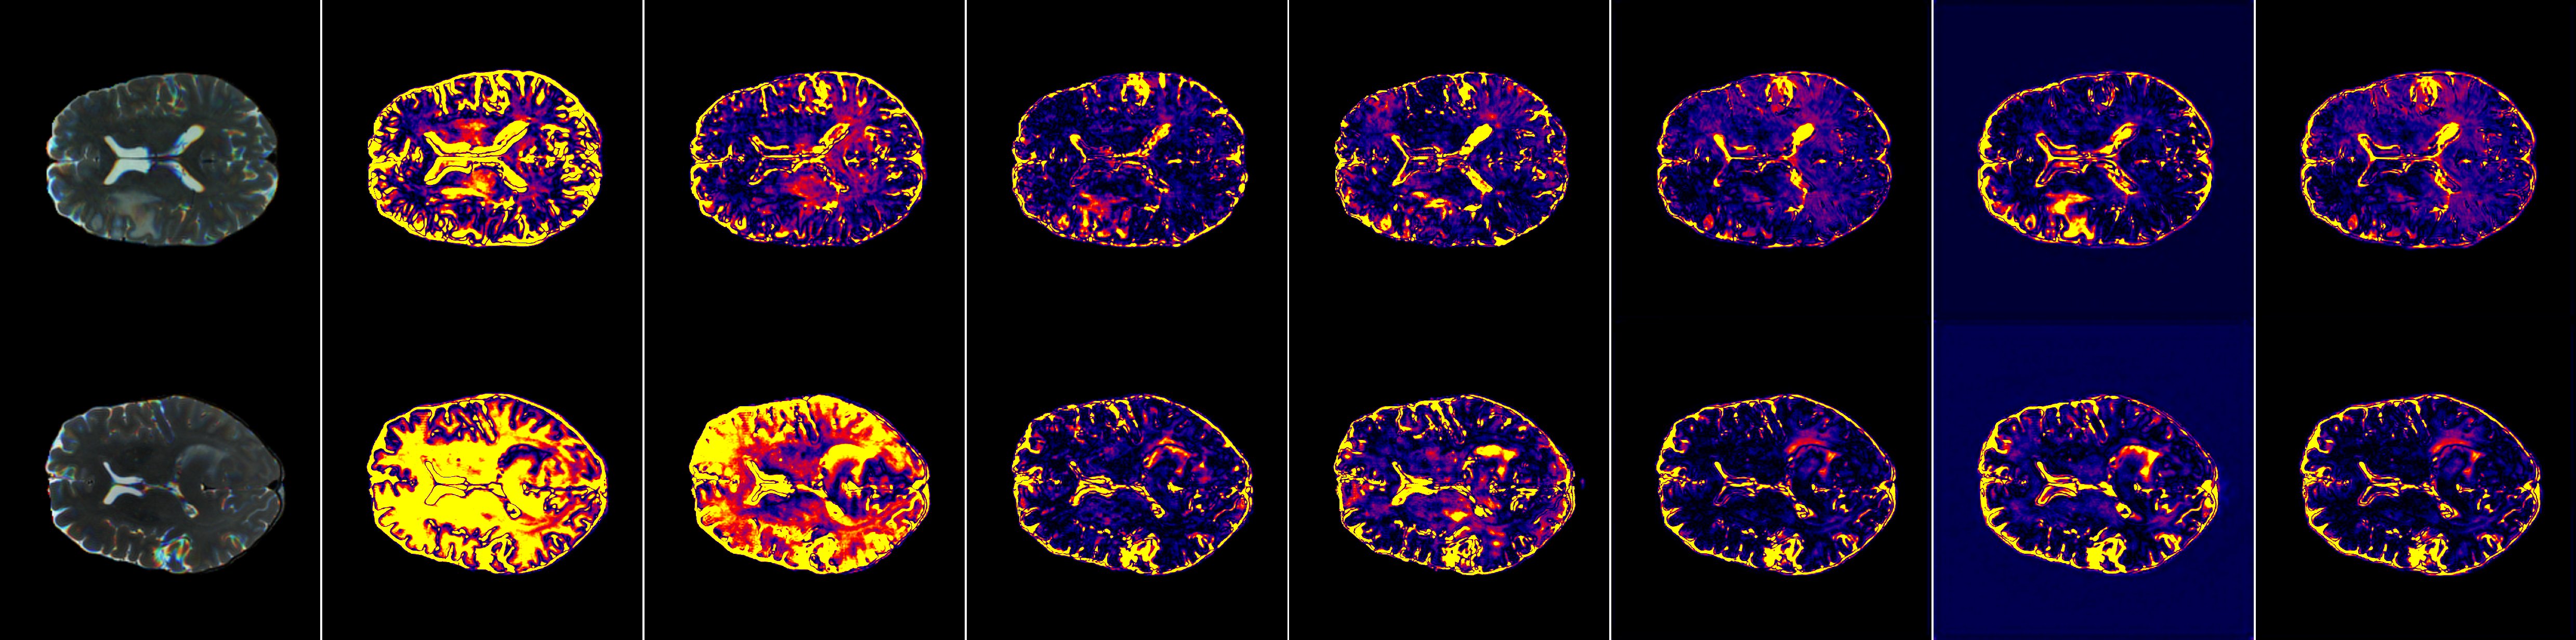

Refer to caption

Figure 7: Comparison of error heatmaps (Part 2/2), provided as a supplementary visualization to the main experimental error analysis.